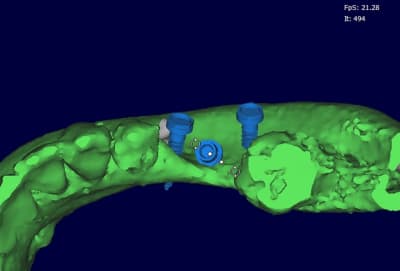

photo

1-2 positionnement des vis pas tout à fait pareil que sur le soft de planification...

ici, les perforations sont beaucoup plus grosses car l'os était nettement moins bien vascularisé et beaucoup plus corticalisé que dans le 1er cas

3- fixation sur la paroi vestibulaire

4- comblement en abondance avec autogène et bioos

5- sutures (patiente vu aujourd'hui, ça tient)